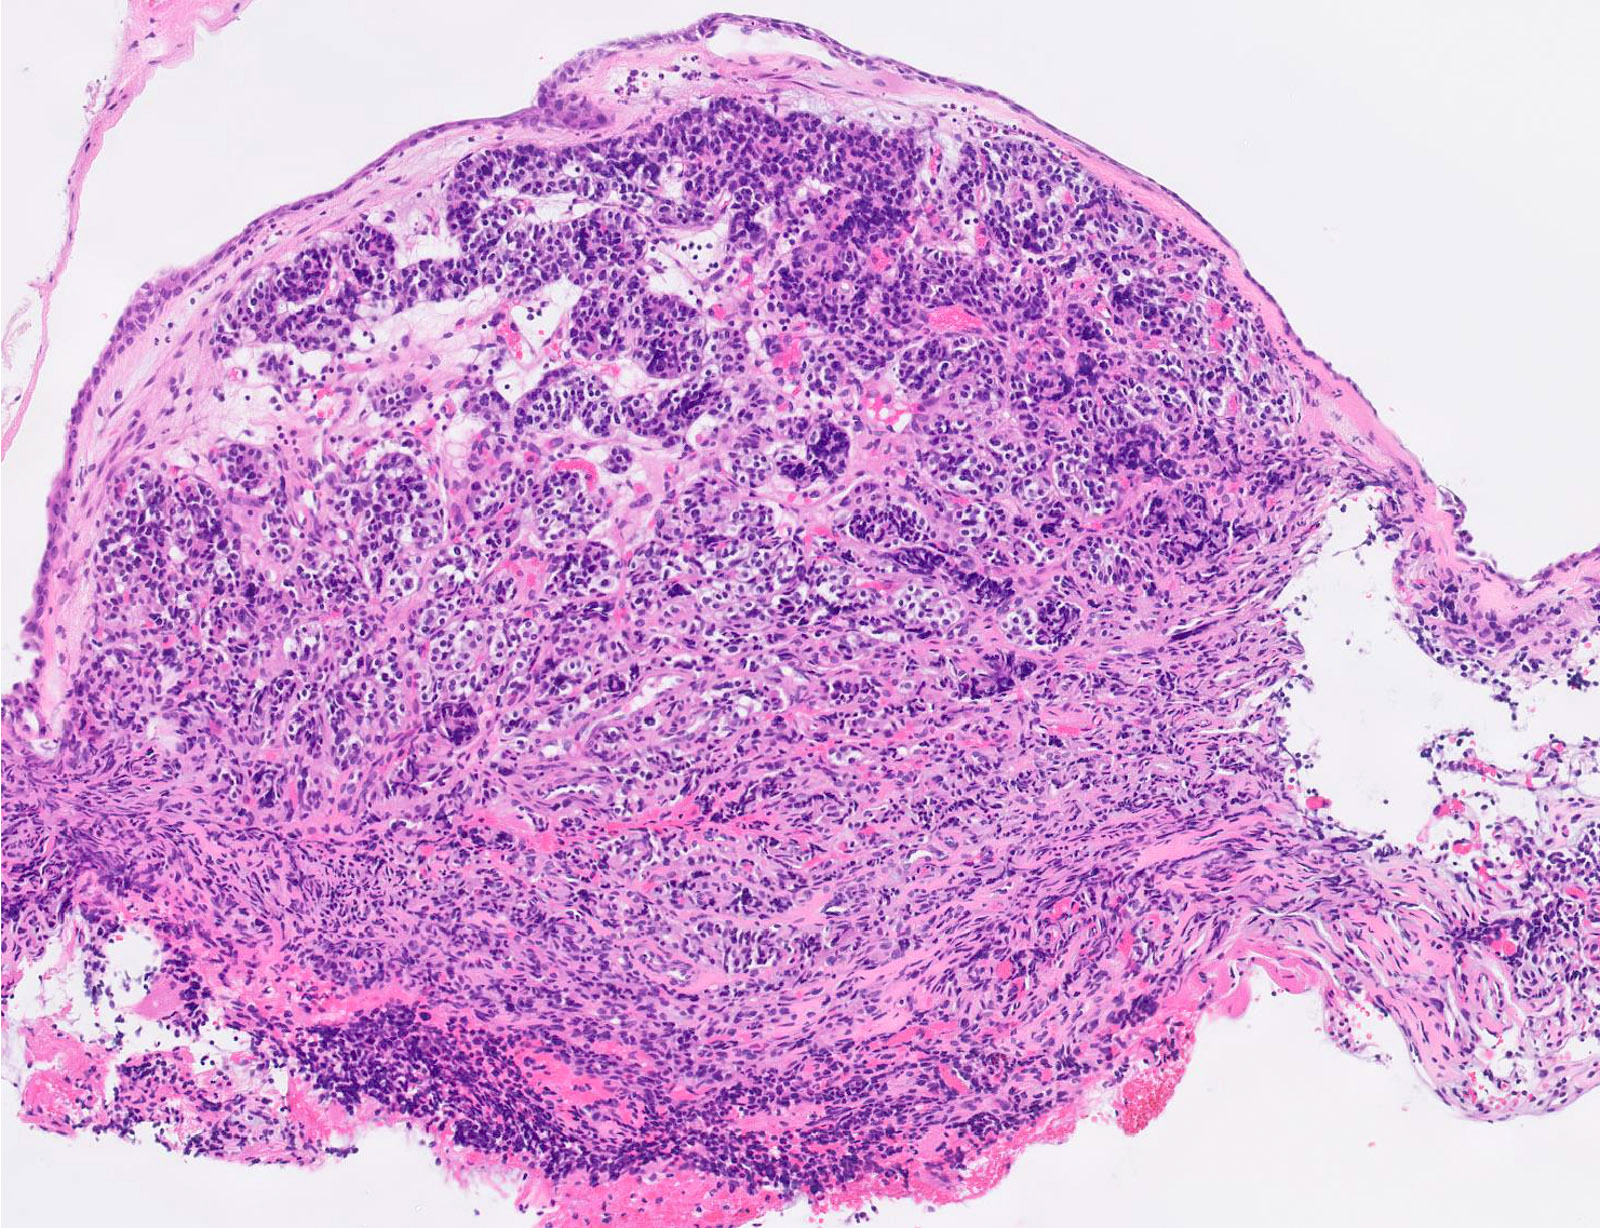

Microscopic (histologic) description

- Diagnostic criteria

- Neuroendocrine tumor with size ≥ 5 mm with < 2 mitoses/2 mm2 and absence of necrosis

- Neuroendocrine growth pattern (organoid, trabecular, rosette formation, nested) or pseudoglandular, follicular and papillary growth

- Tumor cells are uniform with a polygonal shape, round to oval nuclei with salt and pepper chromatin as well as inconspicuous nucleoli and moderate to abundant eosinophilic cytoplasm

- Stroma is fine and highly vascularized; hyalinization, cartilage or bone formation are possible

Microscopic (histologic) images

Contributed by Philippe Joubert, M.D., Ph.D., Jijgee Munkhdelger, M.D., Ph.D. and Andrey Bychkov, M.D., Ph.D.